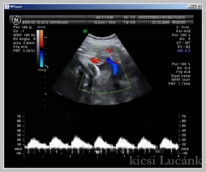

luca08

728 X 603

57 KB |